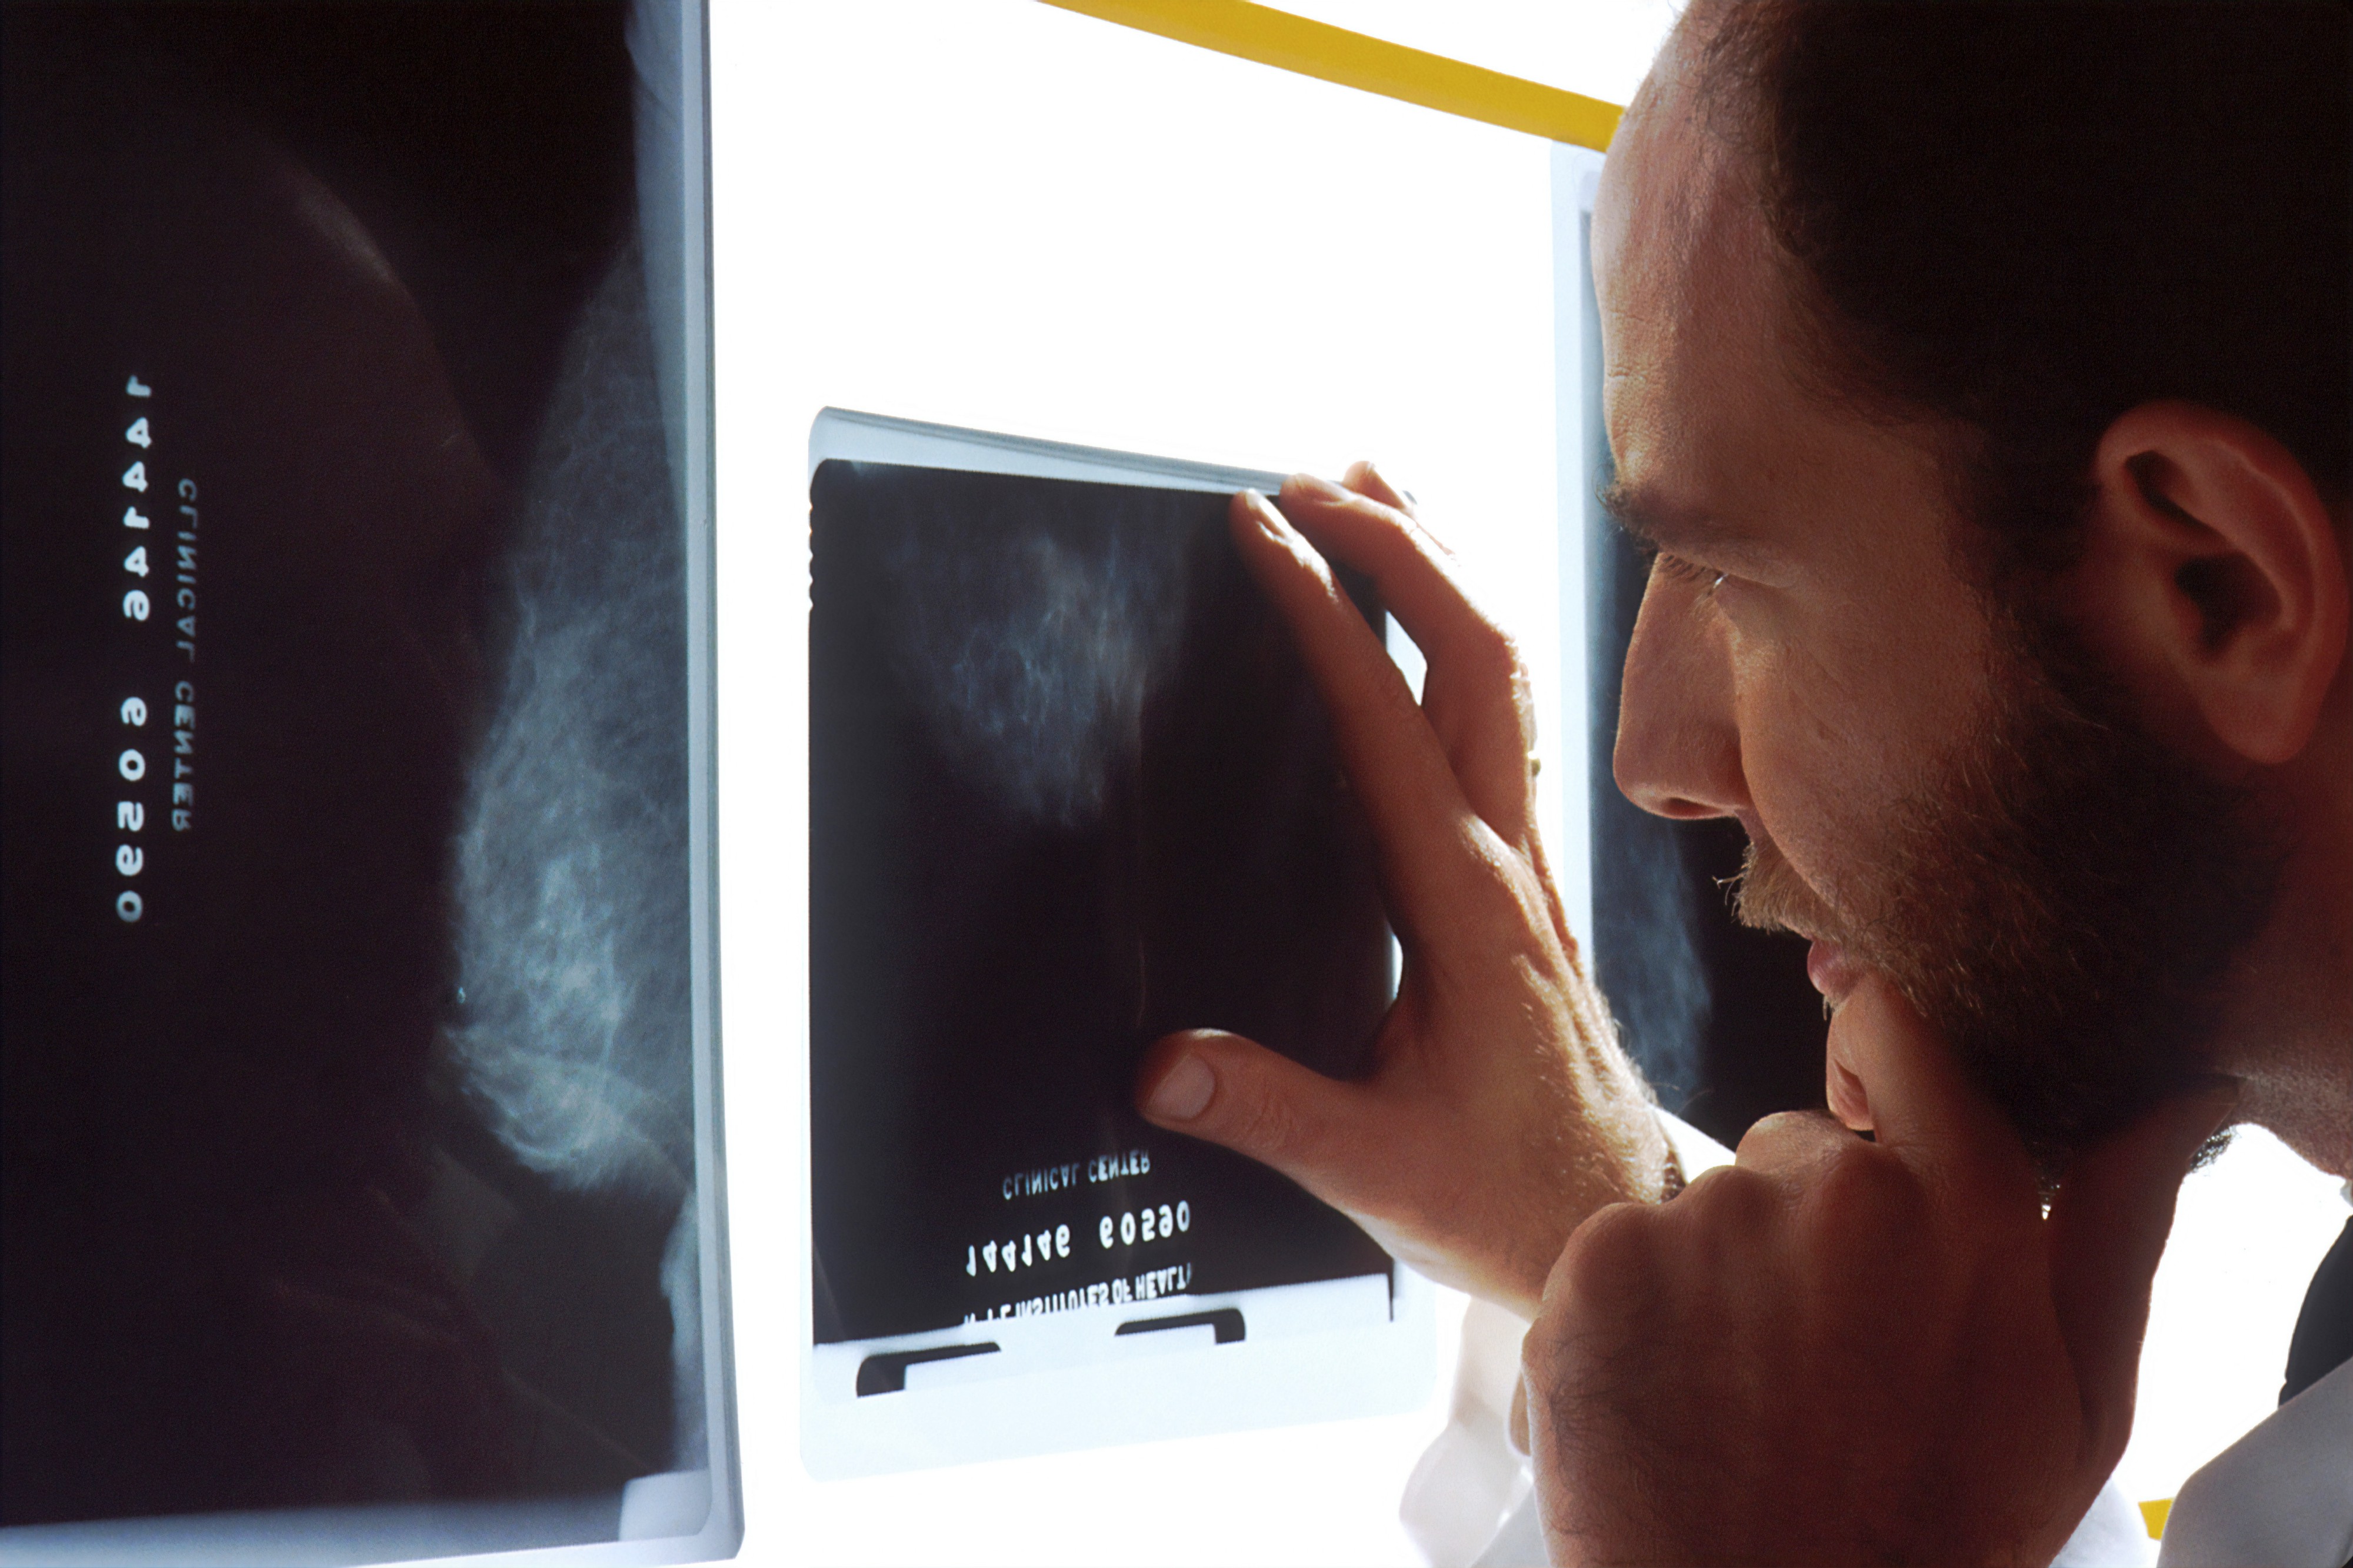

Vara, for example, is a Vertical AI Startup that identifies breast cancer on x-rays. Vara is the first company that has received federal approval to use its AI solution to assist radiologists. The company is a prime example of a Vertical AI Company that completes the full Data Science workflow to deliver an innovative AI-based product.

例如, Vara是一家垂直AI初创公司,可以通过X射线识别乳腺癌。 瓦拉(Vara)是第一家获得联邦批准使用其AI解决方案来协助放射科医生的公司。 该公司是Vertical AI Company的一个典型例子,该公司完成了完整的Data Science工作流程以交付基于AI的创新产品。

Vertical AI Startups include domain experts in key positions such as product roles. For example, it is highly likely for a company that builds an automated cancer detection product to have in-house radiologists and/or oncologists. — Sahar Mor, Entrepreneur in stealth mode

垂直AI初创企业包括关键职位(例如产品角色)的领域专家。 例如,一家制造自动化癌症检测产品的公司很可能会拥有内部放射科医生和/或肿瘤科医生。 —隐身模式下的企业家Sahar Mor

However, it is harder for Vertical AI Startups to adjust their product to serve adjacent use-cases. For Vara, which excels at identifying breast cancer, it is not trivial to switch the task to detect brain cancer. AI models perform well in their narrow tasks. Vara could train a new AI model to detect brain cancer from a new dataset, but still reuse their existing model development pipeline.

但是,垂直AI初创公司很难调整其产品以适合相邻的用例。 对于擅长识别乳腺癌的瓦拉(Vara)来说,切换检测脑癌的任务并非易事。 AI模型在狭窄的任务中表现良好。 Vara可以训练新的AI模型来从新数据集中检测脑癌,但仍可以重用其现有的模型开发流程。